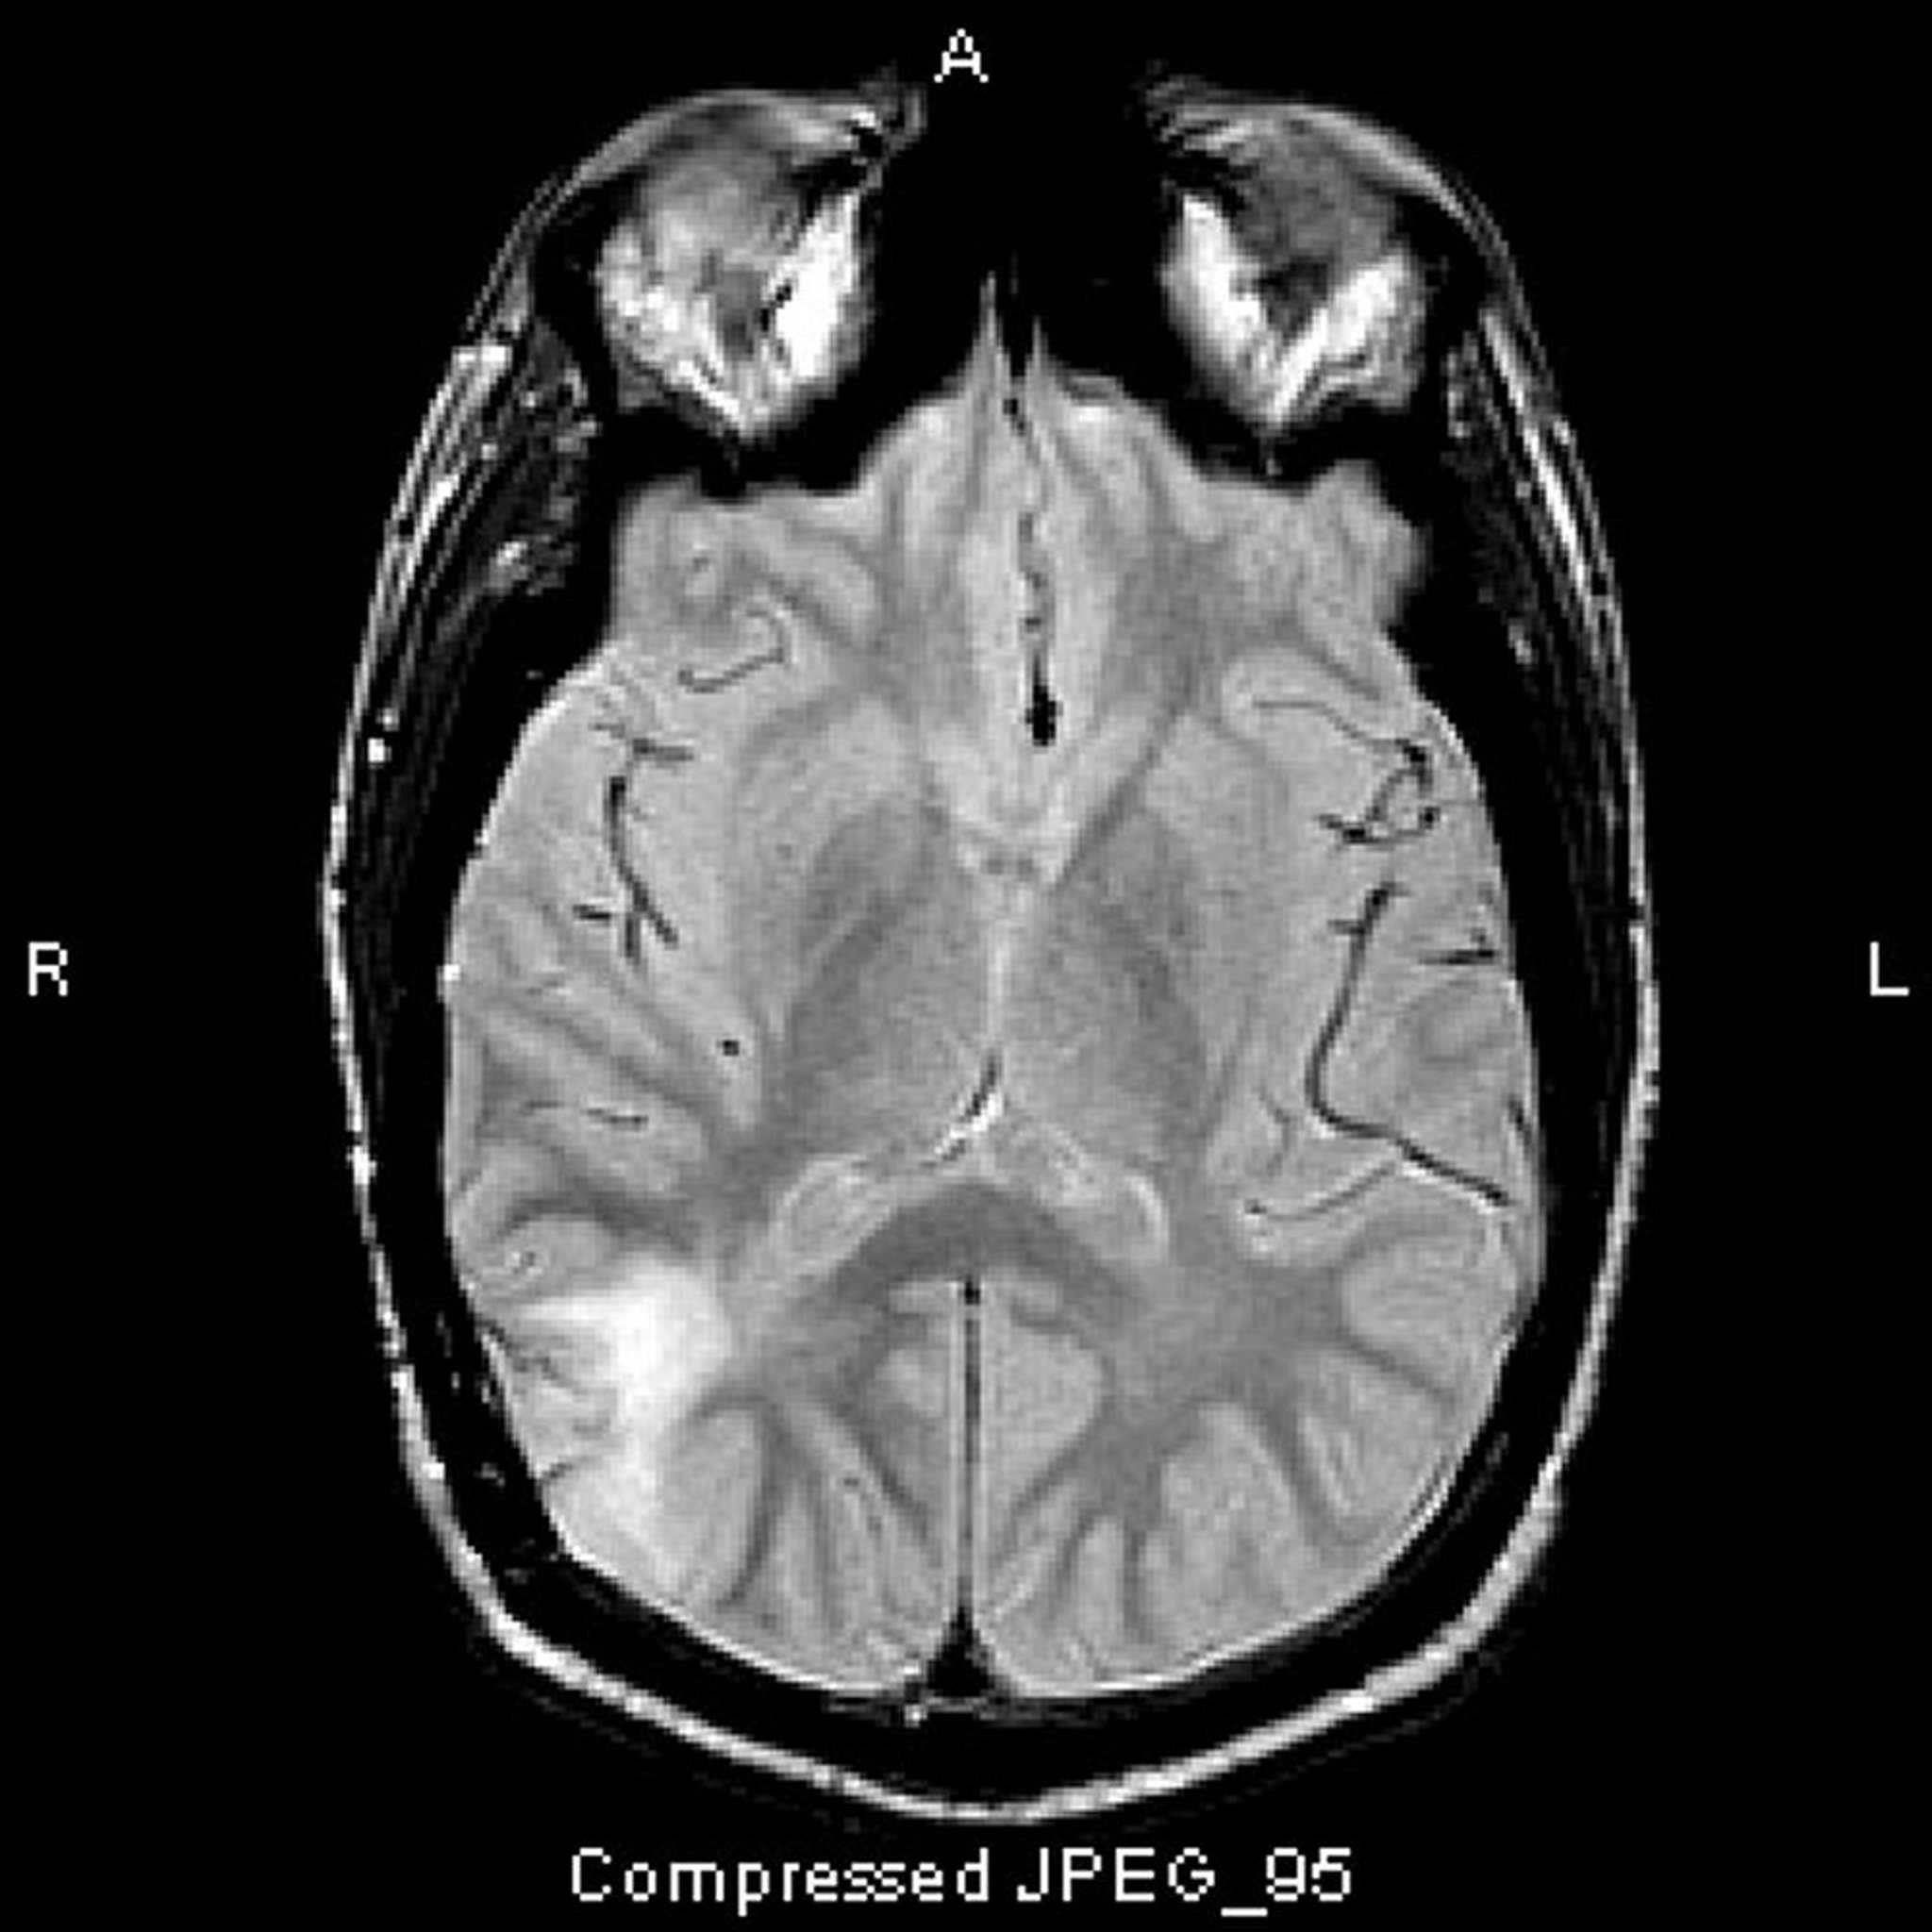

退形成性星細胞腫

このT2-FLAIR MRI画像では,側頭葉後部に白い高信号域が認められる。この信号は造影剤によって増強されない。退形成性(グレードIII)星細胞腫である。

Image courtesy of William R.Shapiro, MD.